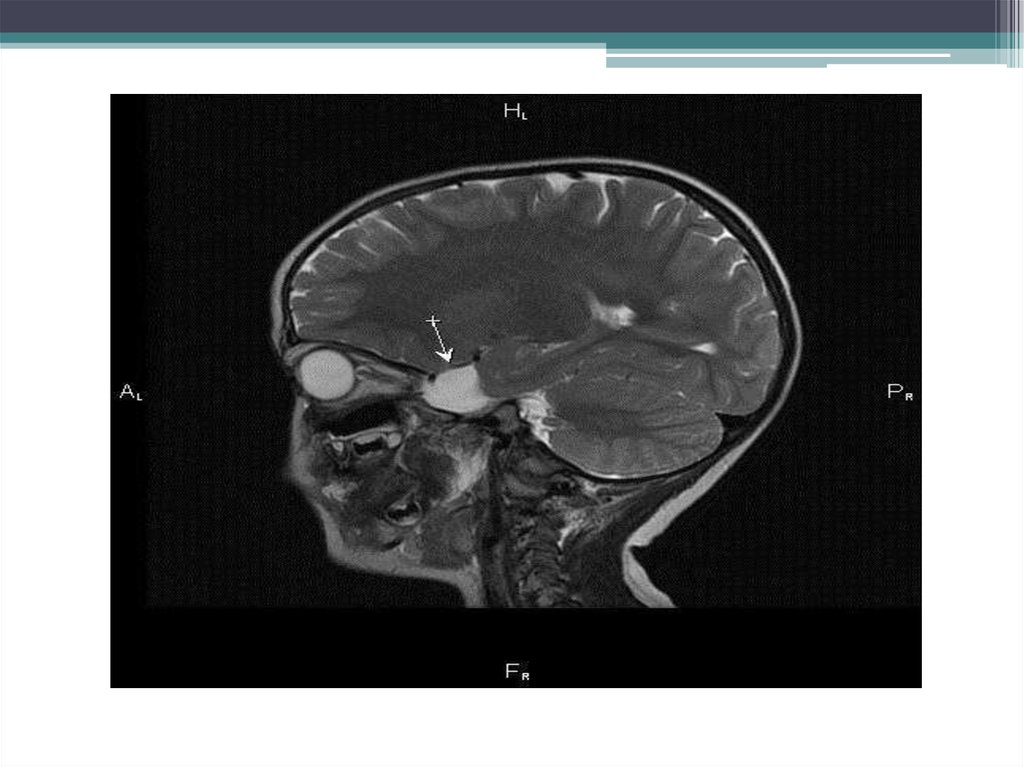

• Пациент К., 2 года.

Обратилась жалобами на задержку психоречевого развития.

Была проведена МРТ головного мозга с

наркозом.

В медиобазальных отделах левой височной

доли выявлена ликворная полость, широко

сообщающаяся с субарахноидальным

пространством.